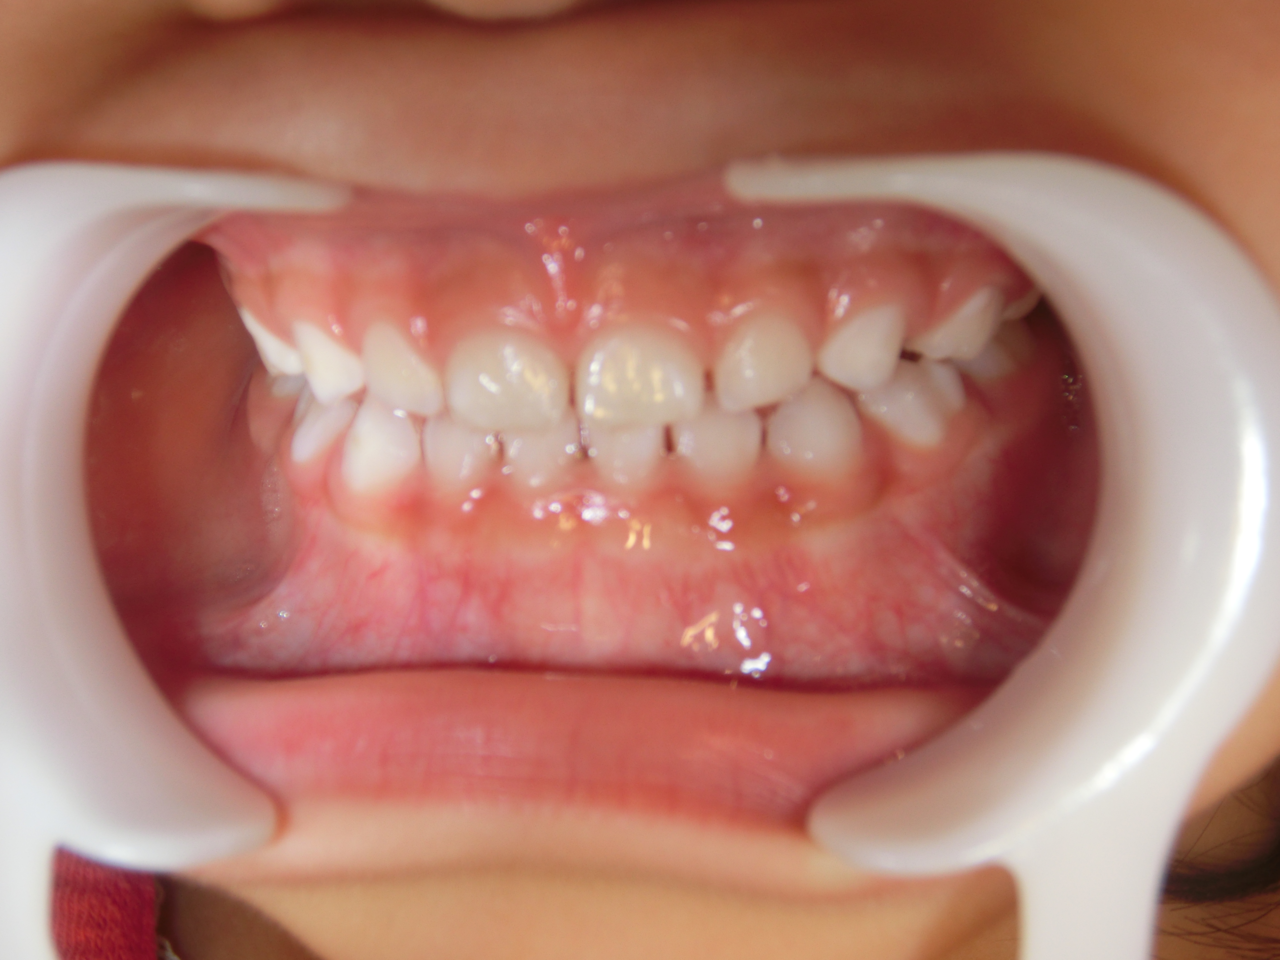

治療前

治療説明 歯科矯正で取り外し可能な矯正方法である床矯正で治療しました

治療期間 4年

治療費用200000 円

治療後

治療の副作用(リスク)歯の動き方には個人差があり、予想された治療期間が延長する可能性があります。。床矯正の使用状況、矯正歯科治療には患者さんの協力が必要であり、それらが治療結果や治療期間に影響します。2次矯正が必要になる場合もあります。